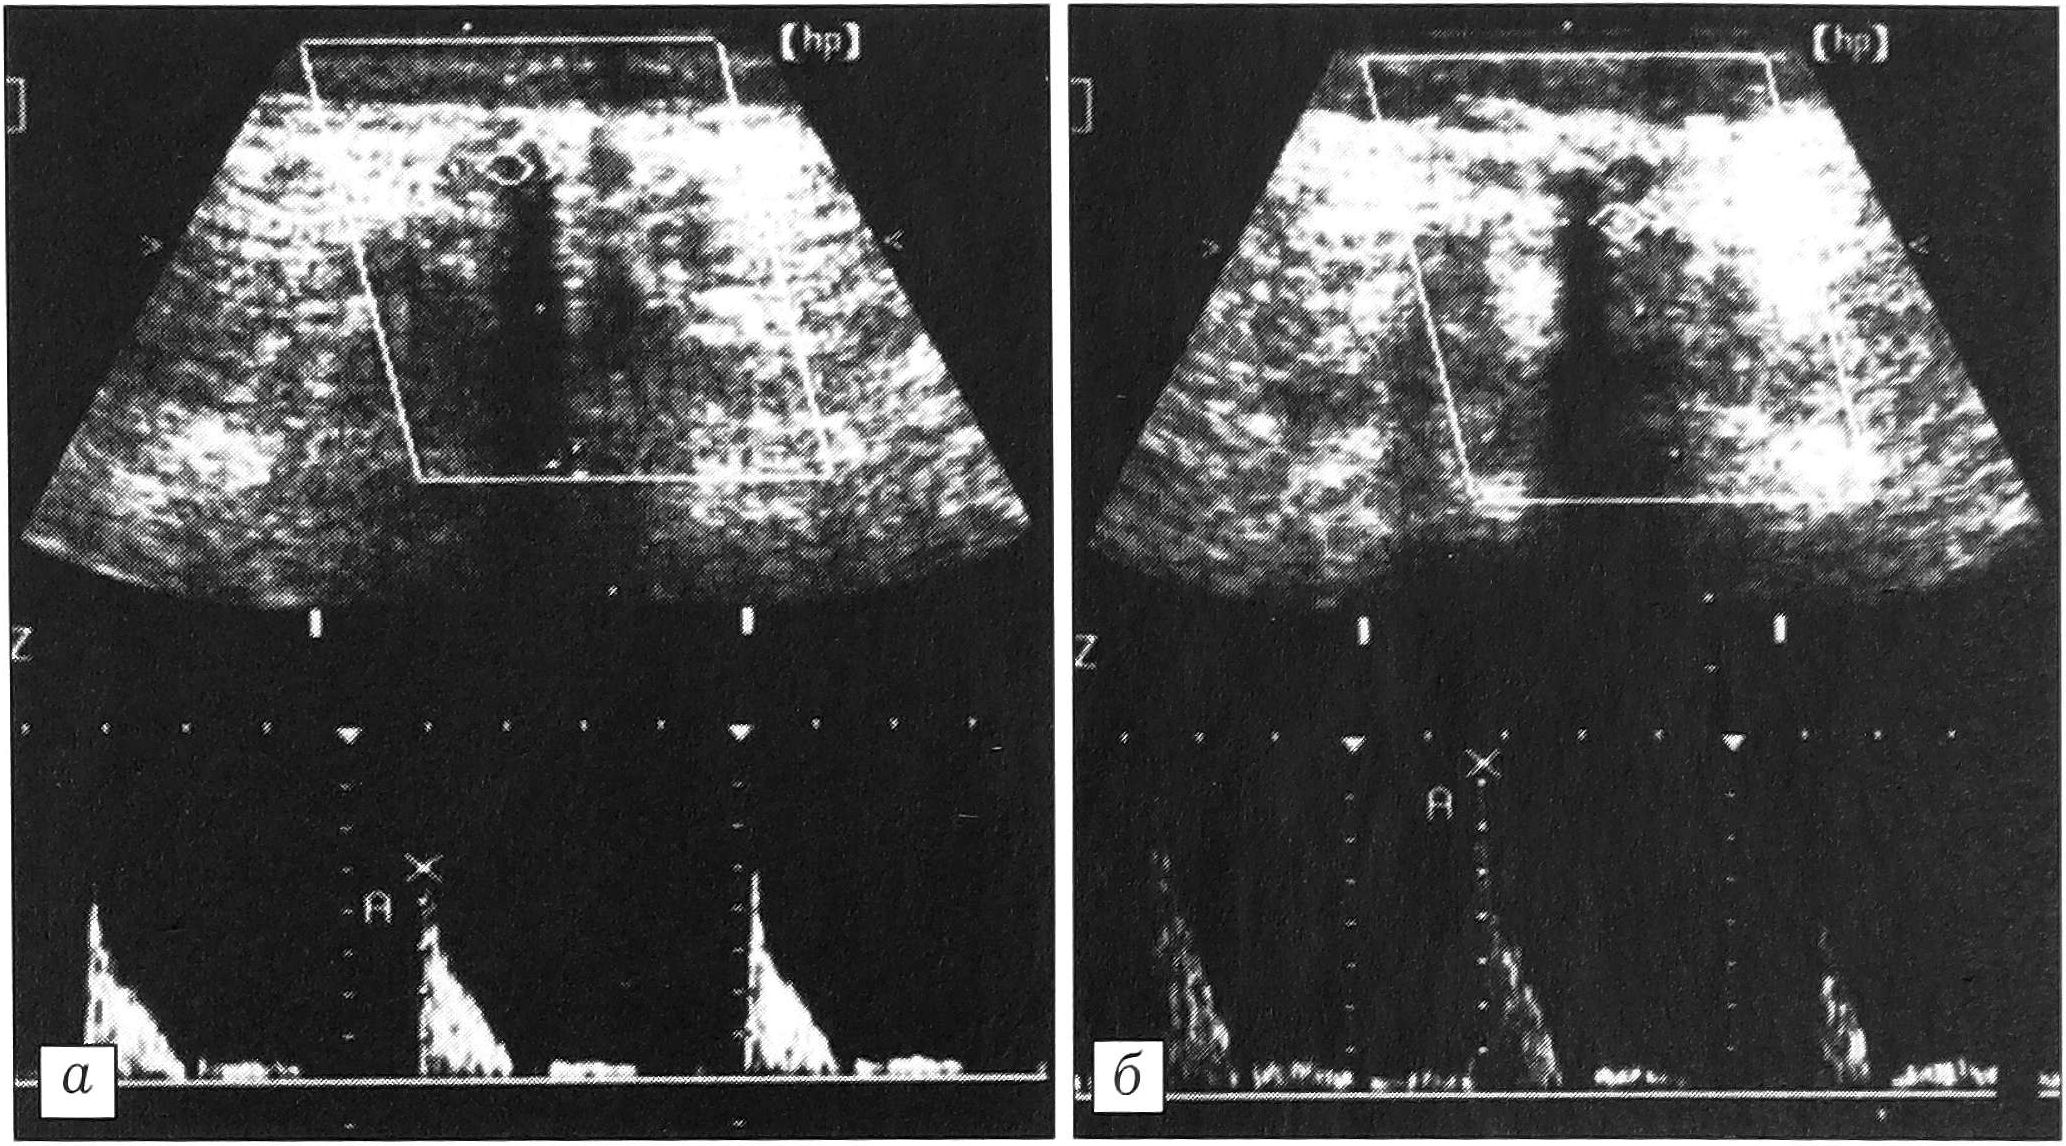

Остистые связки. Обследовано 15 пациентов с клиникой повреждения или перегрузки остистых связок и 20 человек без подобных симптомов.

Межостистые связки при сонографии имеют вид плотноволокнистых структур, расположенных между остистыми отростками. Более плотный задний край их — надостистая связка. При хронической перегрузке остистых связок определяются рубцовые изменения надостистых и межостистых связок, кальцификаты в их толще и оссификаты в местах костных прикреплений (рис. 5, а). В 2 случаях обнаружен лигаментоз надостистой связки (рис. 5, б). Рентгенологически при этом наблюдались признаки синдрома Бааструпа. Наличие дефекта в остистой связке, увеличивающегося при сгибании позвоночника, подтверждает диагноз разрыва связки.

Как показал анализ полученных данных, длина остистых связок, или величина межостистого промежутка, весьма индивидуальна. Вместе с тем у каждого пациента длина остистых связок в поясничном отделе позвоночника практически не различается (разница составляет в среднем 0,06 мм). Поэтому оптимальным является сравнение длины остистых связок у одного и того же обследуемого. При хронической микротравматизации связок отмечаются увеличение межостистого промежутка, выраженные дегенеративные изменения связок (рис. 5, в).

Рис. 5. Ультрасонограммы остистых связок поясничного отдела позвоночника. а — рубцовые изменения, кальцификаты межостистой связки; б — лигаментоз надостистой связки; в — удлинение остистых связок вследствие повторных микротравм.

В норме кровоток в проекции связок не определялся. При остром разрыве межостистой связки над местом ее повреждения визуализировался участок повышенной васкуляризации с распространением сосудов в ткань связки.